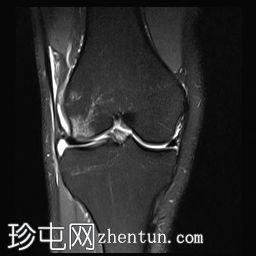

冠状位PD序列

脂肪抑制序列

前交叉韧带(ACL)完全断裂,PDFS和T2加权像显示韧带中部纤维信号增高,残余纤维下垂于胫骨平台,冠状位可见空切迹征。

此外,胫骨平台后外侧和股骨髁前外侧可见骨挫伤异常信号。

外侧副韧带也存在水肿,纤维断裂,提示为III级损伤。

膝关节积液,主要位于髌上囊。